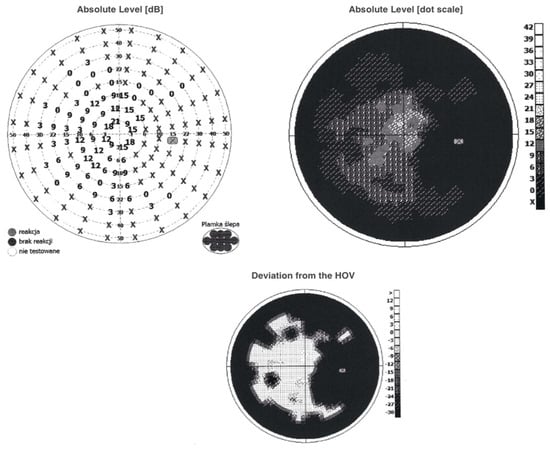

The visual field examination was notable for observed abnormalities in the central visual field—a large central scotoma involving the blind spot reaching 5 degrees from the fixation point. Peripheral constrictions in all quadrants were also present (Figure 4).

Figure 4.

A visual field evaluation revealed large scotoma involving the blind spot and peripheral constrictions in all quadrants. Examination performed on the day of the patient’s hospital admission. HOV; hill of vision.